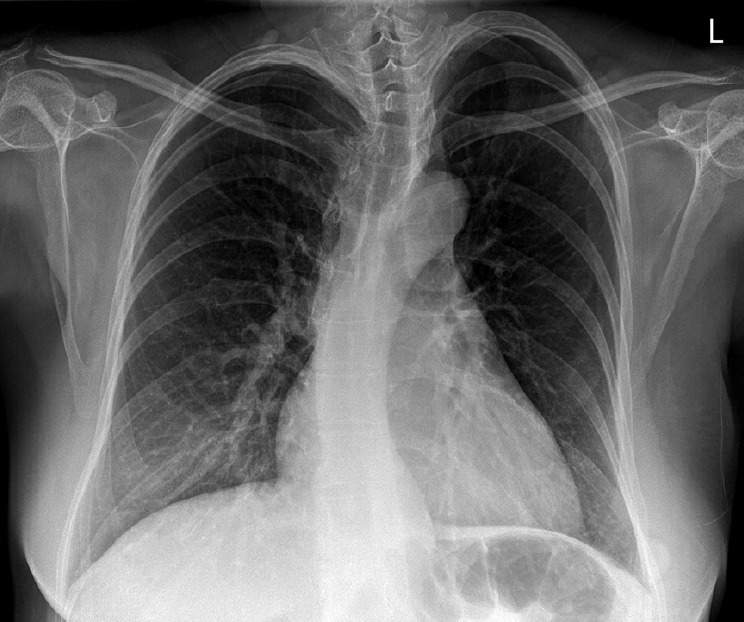

Aortic dissection in pregnant patients results in an inpatient mortality rate of 8.6%. Owing to the pronounced mortality rate and speed at which aortic dissections progress, efficient early detection methods are crucial. Here, we highlight the importance of early chest computed tomography (CT) for differentiating aortic dissection from pulmonary embolism in pregnant patients with dyspnea. We present the unique case of a 38-year-old pregnant woman with elevated D-dimer and N-terminal pro-brain natriuretic peptide (NT-proBNP) levels, initially suspected of having a pulmonary embolism. Initial transthoracic echocardiography did not indicate aortic dissection. Surprisingly, after an emergency cesarean section, a chest CT scan revealed a DeBakey type I aortic dissection, indicating a diagnostic error. Our findings emphasize the need for early chest CT in pregnant patients with dyspnea and elevated D-dimer and NT-proBNP levels. This case report highlights the critical importance of considering both aortic dissection and pulmonary embolism in the differential diagnosis of such cases, which will inform future clinical practice.

Abstract Image